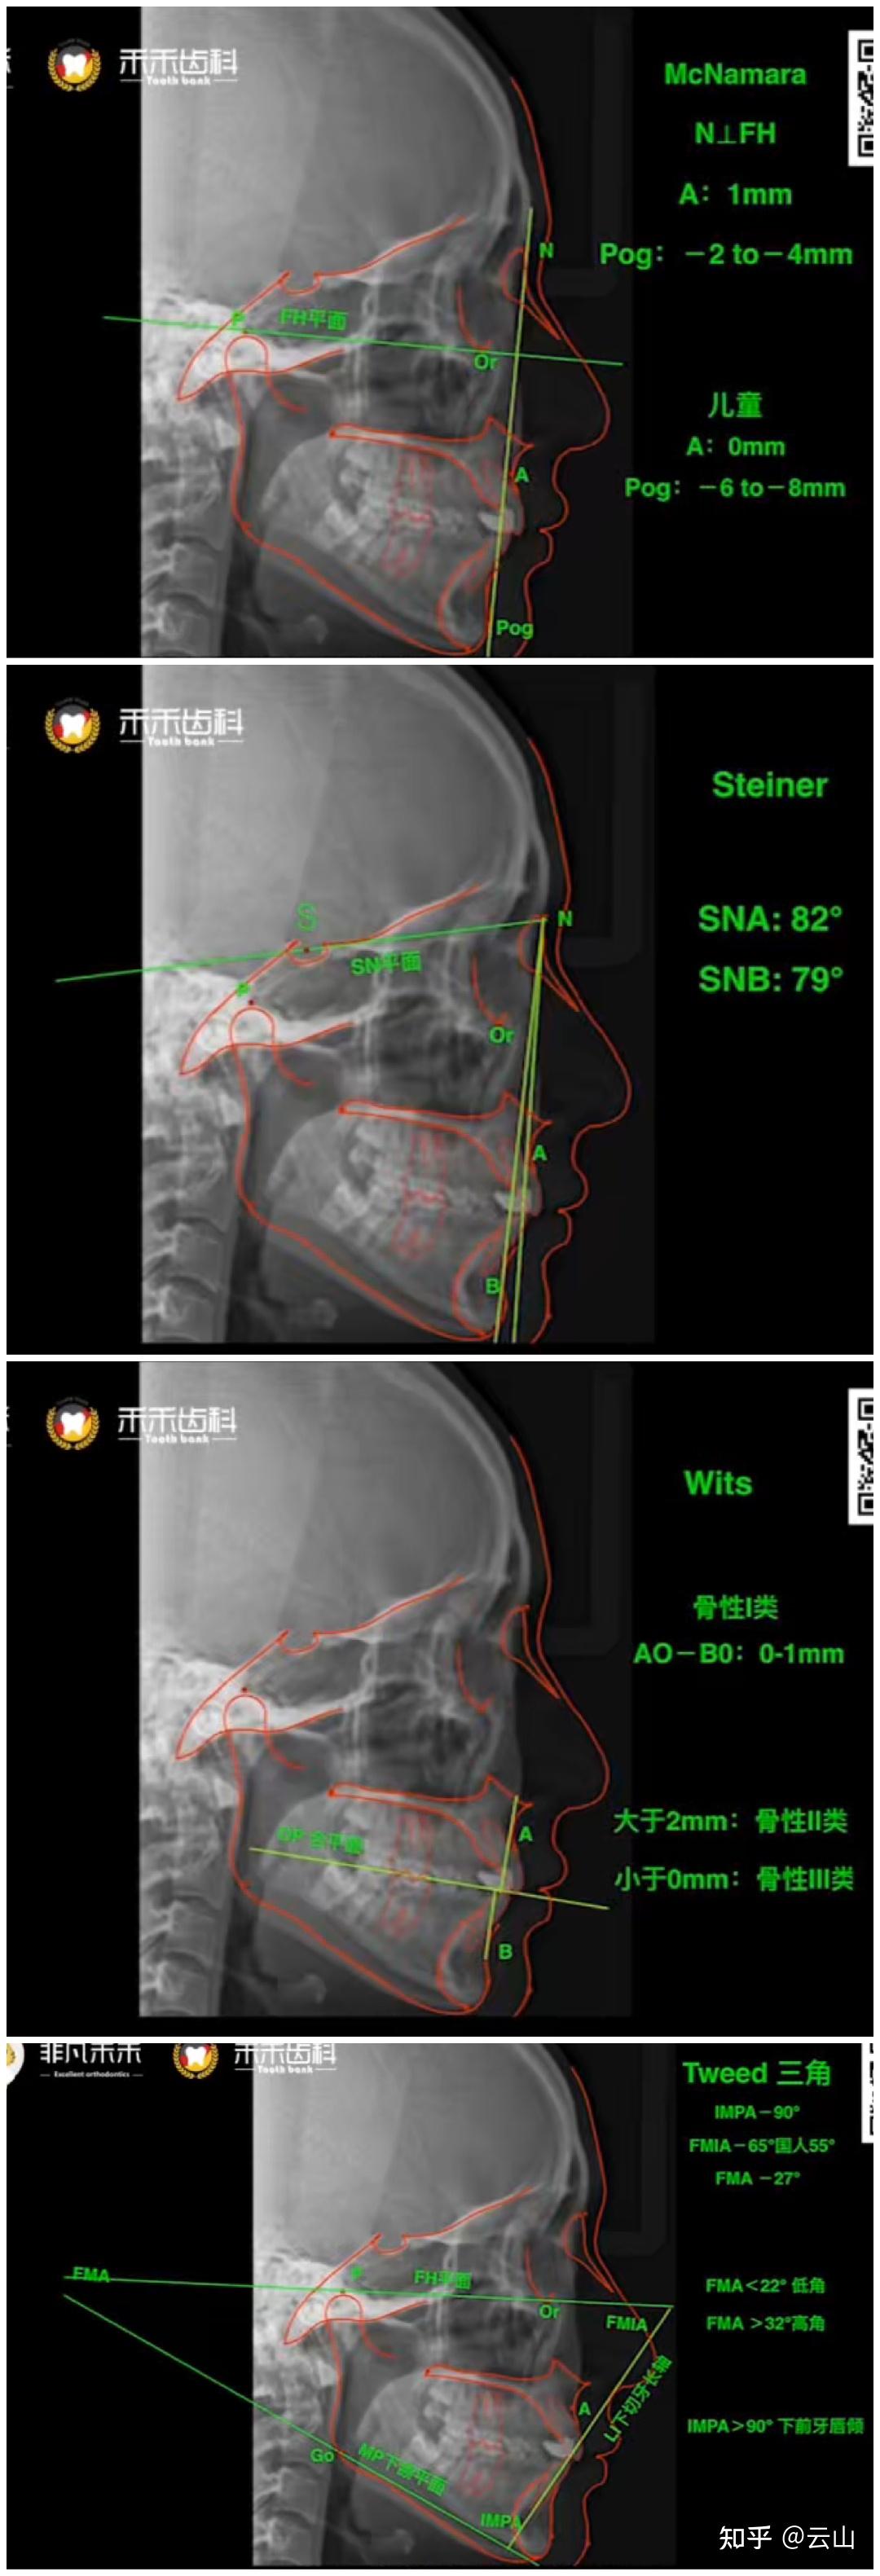

正畸头影测量标准值与项目

图片尺寸2435x1414